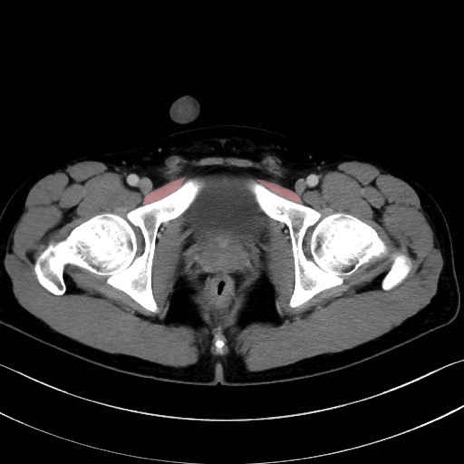

恥骨筋 (Pectineus)